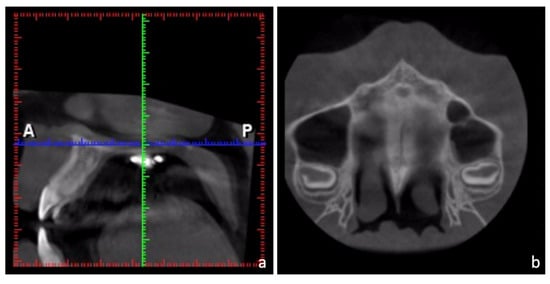

- Lee, J.A.; Ahn, H.W.; Oh, S.H.; Park, K.H.; Kim, S.H.; Nelson, G. Evaluation of interradicular space, soft tissue, and hard tissue of the posterior palatal alveolar process for orthodontic mini-implant, using cone-beam computed tomography. Am. J. Orthod. Dentofac. Orthop. 2021, 159, 460–469. [Google Scholar] [CrossRef] [PubMed]

- Kim, H.J.; Yun, H.S.; Park, H.D.; Kim, D.H.; Park, Y.C. Soft-tissue and cortical-bone thickness at orthodontic implant sites. Am. J. Orthod. Dentofac. Orthop. 2006, 130, 177–182. [Google Scholar] [CrossRef] [PubMed]